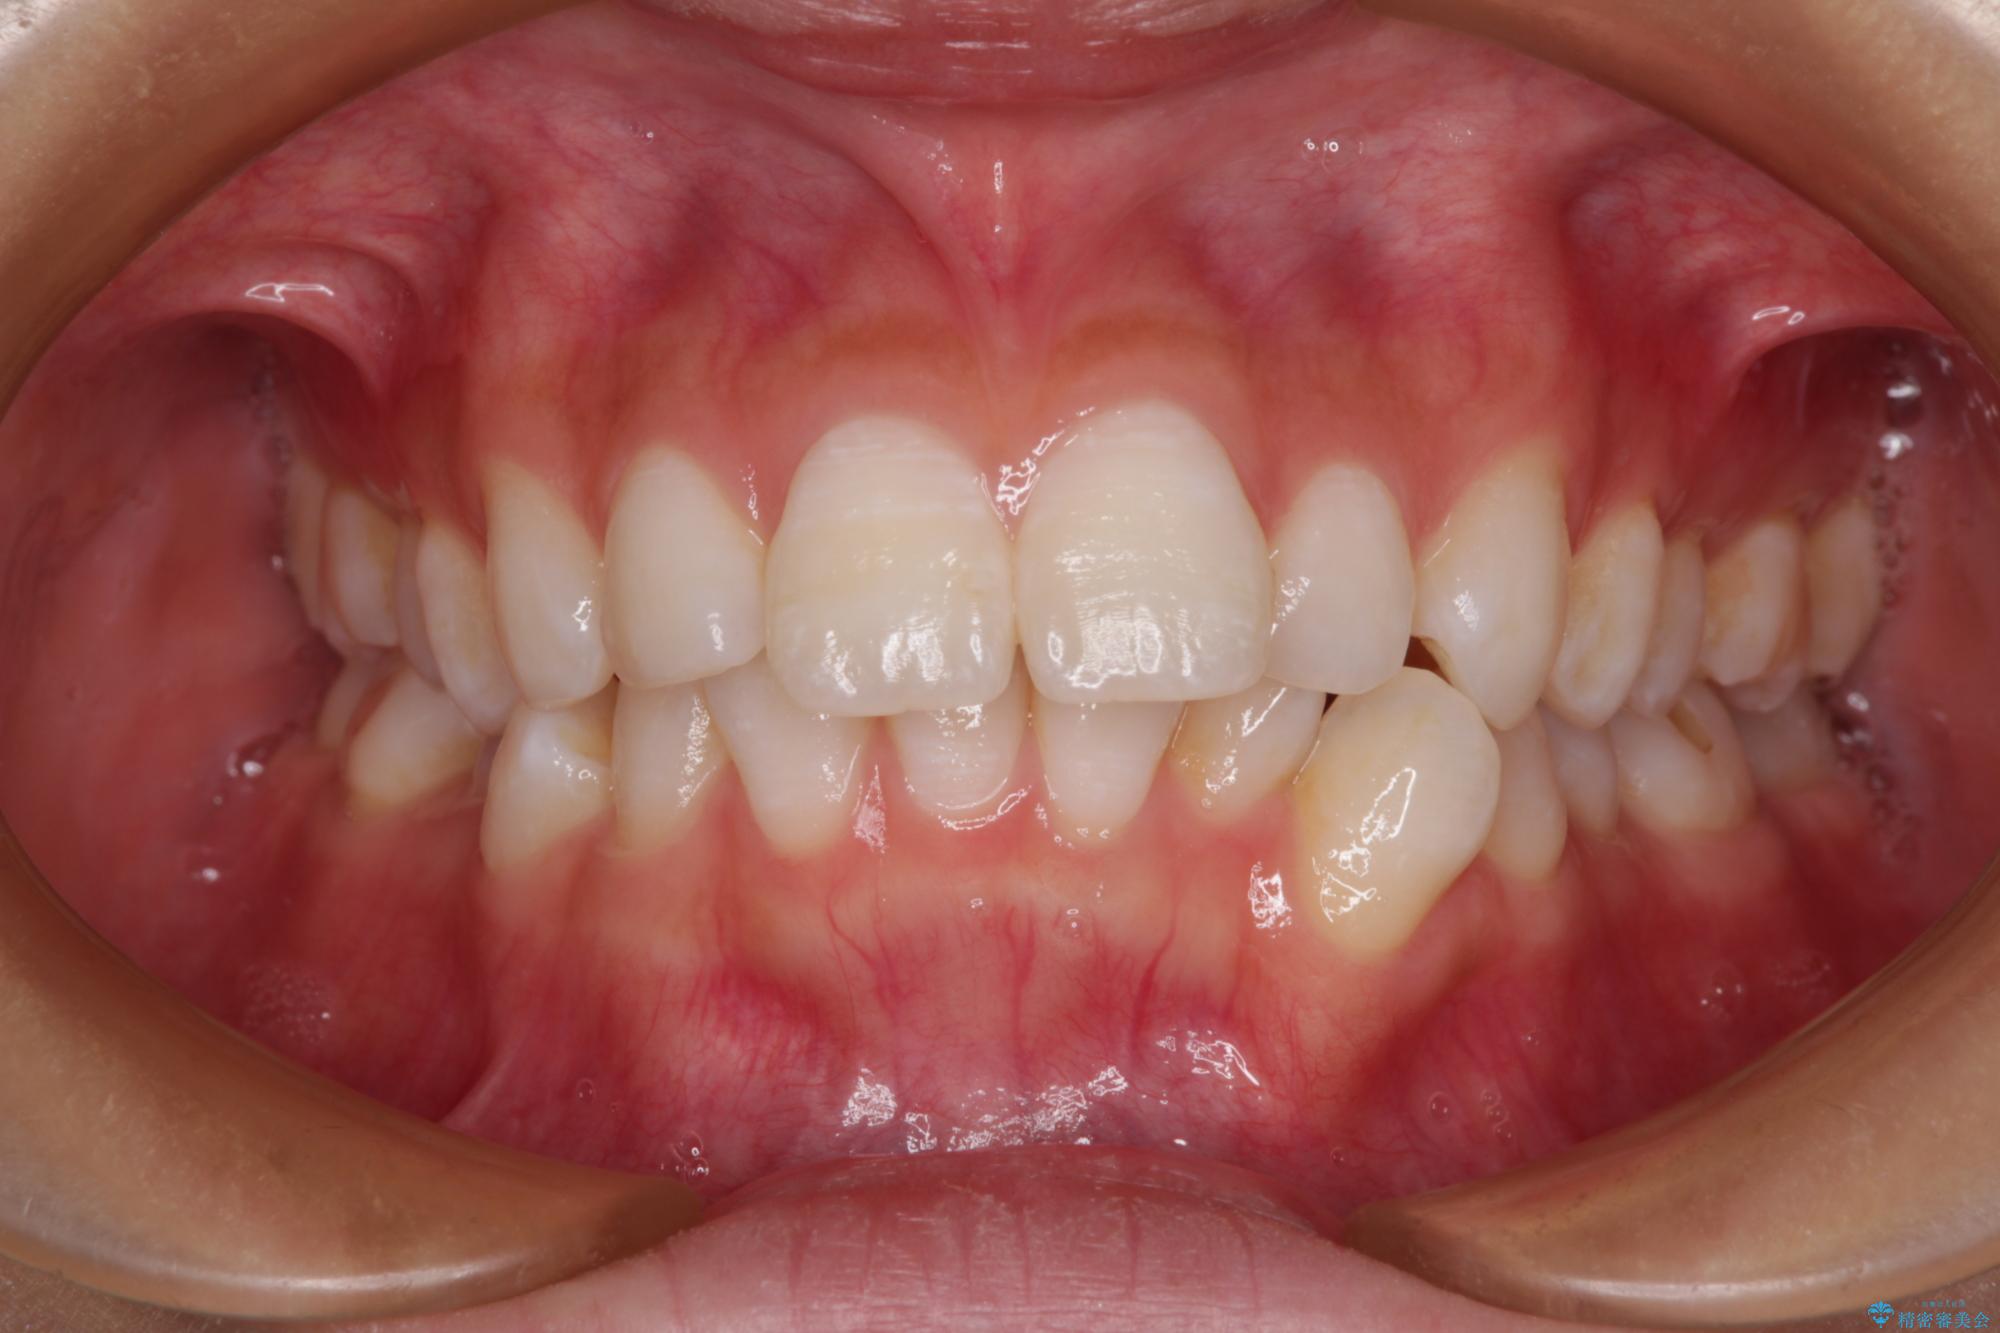

- 口を閉じたときに飛び出してしまう上顎前歯を気にして来院された患者様です。

下顎はデコボコが気になっていたため、上下左右第一小臼歯4本を抜去して、ワイヤー装置にて口元の突出感を改善するよう矯正治療を行うこととしました。

下唇に前歯が当たって跡が残ってしまう状態でしたが、スッキリとした口元に仕上げることができました。